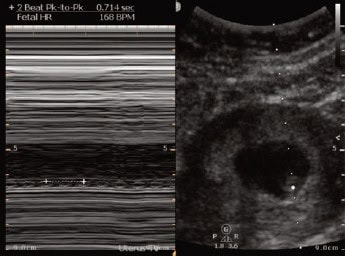

A 28-year-old female presents to urgent care with mild left lower quadrant (LLQ) abdominal pain that began earlier in the day. The discomfort is dull, intermittent, and non-radiating. She denies vaginal bleeding, fever, nausea, vomiting, or urinary symptoms. Her last menstrual period was approximately 2 months ago, although she reports a history of irregular cycles.

She appears well and is hemodynamically stable. An abdominal exam reveals mild LLQ tenderness without rebound or guarding. A pelvic exam shows no discharge, bleeding, adnexal tenderness, or cervical motion tenderness. No masses are appreciated. A urine pregnancy test performed in the clinic returns positive. Given concern for ectopic pregnancy, a transabdominal point-of-care ultrasound (POCUS) is performed.

View the images above and consider the likely diagnosis and next steps. The resolution of the case is described on the following page.